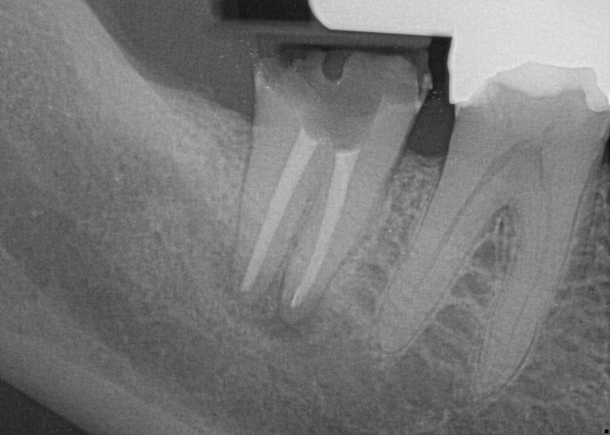

Fig 8. Gold crown removed, dentin excavated, canals shaped and filled.

Figure 8

Fig 9. 33 days postoperative fiber-post placement and CAD crown.

Figure 9

The patient returned for final evaluation of the provisional calcium-hydroxide endodontic therapy and resolution of the infection (33 days postoperatively). Fistula was not present; the tooth was not sensitive to percussion or mastication. The gold crown was removed using a high-speed metal cutting bur, the remaining caries were excavated conservatively, and the endodontic therapy was completed. Placement of glass-fiber reinforced composite and composite core buildup took place. The natural tooth structure to receive the glass-fiber post and a long-term restoration was available (Figure 8). Within one appointment, the tooth was restored (Figure 9). The patient was instructed to return for clinical and radiographic evaluation after 6 to 12 months to determine progression of periodontal healing. At that time, if the healing were adequate and the tooth were stable, evaluation of the tooth would be considered every 3 to 4 years.7